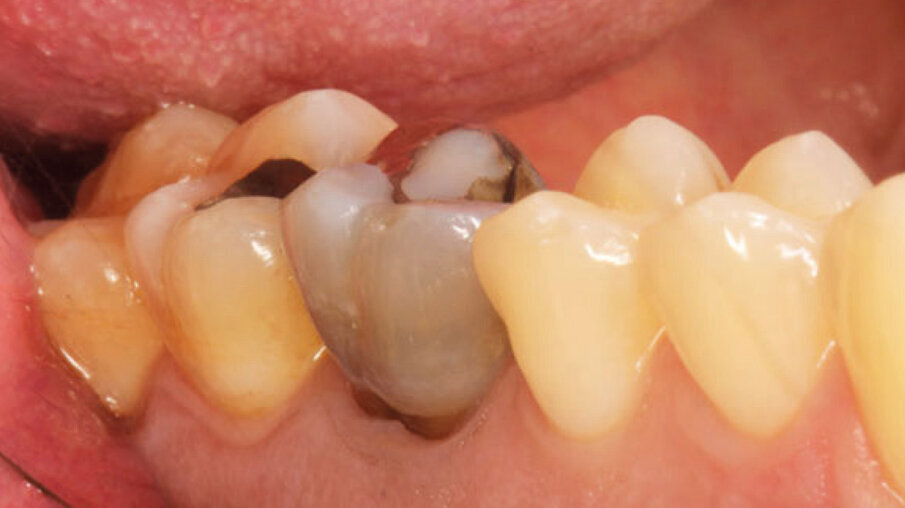

Un paziente maschio (ASA I), senza patologie croniche sistemiche e non fumatore, è stato sottoposto all’estrazione dell’elemento 16 a seguito del fallimento di terapie endodontiche e dell’impossibilità di eseguire un restauro coronale (Figg. 1a, 1b). Nella selezione del paziente sono stati criteri di esclusione: pregressa radioterapia nel distretto testa/collo, assunzione di farmaci che possano indurre ONJ, disordini ematici coagulativi, bruxismo, scarsa igiene orale domiciliare, occlusione instabile, carie non trattate, malattia parodontale non controllata, denti adiacenti a quelli da estrarre con mobilità di grado I o superiore, aspettative di risultato irreali, impossibilità o non propensi a tornare ai controlli di routine e di follow-up. La situazione dei tessuti è stata valutata pre-operatoriamente tramite radiografia periapicala (Fig. 1c) (VistaScan Mini Plus, Dürr Dental). Tramite la CBCT pre-operatoria è stato possibile fare una programmazione implantare. Sulla base dell’anatomia coronale è stata definita la posizione implantare (OnDemand3D, Cybermed), da questa analisi sono stati decisi anche il diametro e la lunghezza dell’impianto.

Fig. 1b_Foto iniziale vestibolare.